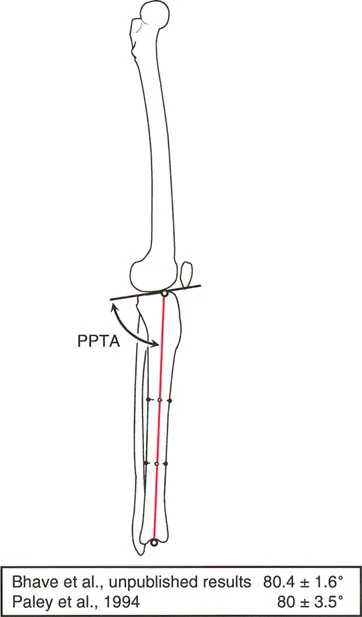

الزاوية الظنبوبية القريبة الخلفية (PPTA)

تقيس PPTA ميلان الجزء الخلفي من سطح عظم الساق العلوي (اللقمة الظنبوبية). وهي الزاوية الخلفية المتكونة بين المحور التشريحي لعظم الساق وخط مفصل الساق القريب في الصورة الشعاعية الجانبية.

* القيمة الطبيعية المقبولة لـ PPTA هي 80 درجة ± 3.5 درجة (أو ما يعادل ميلاناً خلفياً بحوالي 10 درجات عن الخط العمودي).

هذا الميلان الخلفي ضروري لوظيفة الركبة الطبيعية، حيث يؤثر على كيفية عمل الأربطة الصليبية (الأمامية والخلفية) واستقرار الركبة. أي تغيير في هذه الزاوية يمكن أن يزيد من خطر إصابات الأربطة أو يسبب عدم استقرار في الركبة.